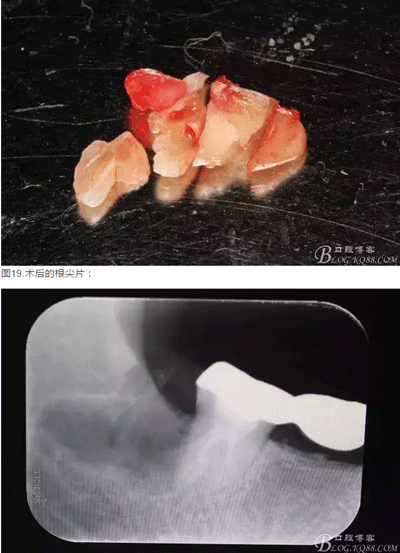

圖18.大卸八塊的牙齒,之所以分這么多塊,就是為了取這些牙體組織的時(shí)候不會(huì)碰到前面的47全瓷冠。